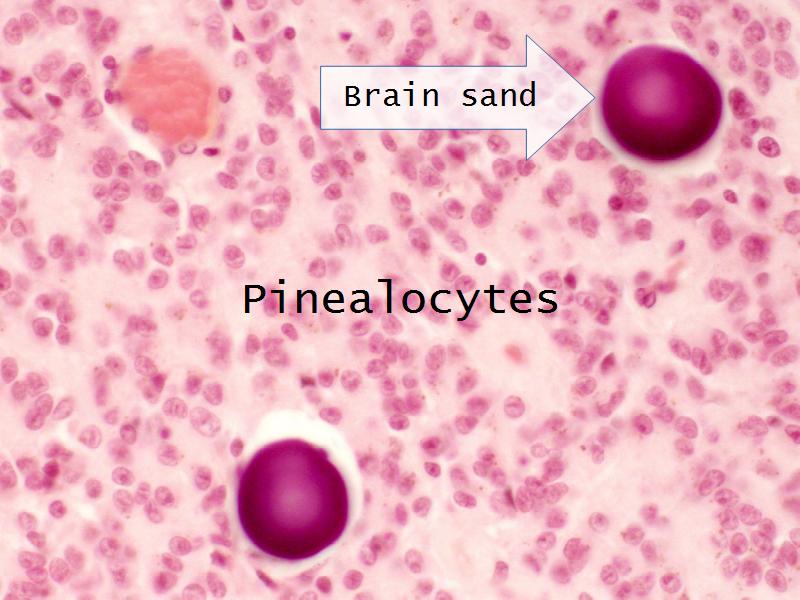

- Slide 34: Pineal gland

Pineal Gland